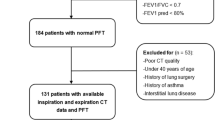

Study subjects

The data used in the present analysis were based on those from a prospective observational study performed at Kyoto University [27, 28]. The inclusion criteria were (1) a smoking history of at least 20 pack-years, (2) COPD diagnosis, and (3) no history of lung resection surgery or other lung diseases, such as bronchial asthma or interstitial lung disease. All male patients who underwent chest inspiratory CT scans and completed lung function testing including spirometry, lung volumes and diffusion capacity measurements, and a CAT questionnaire during an exacerbation-free period were enrolled at Kyoto University Hospital from April 2011 to April 2014. Lung function was measured with a Chestac-65 V (Chest MI Corp., Tokyo, Japan), and chest CT scans were performed with an Aquilion 64 scanner (Toshiba; Tokyo, Japan). Calibration of the CT scanner was routinely performed with air and water phantoms, and the scanning conditions were as follows: 0.5-mm collimation, 500-millisecond scan time, 120 peak kilovoltage, and auto-exposure control. Reconstruction was performed with a high spatial frequency algorithm (FC56) as previously reported [27].